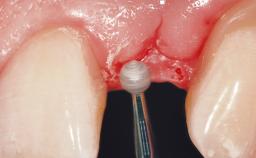

A 30-year-old female patient had lost tooth 21 and was referred to our clinic for consultation and treatment. Due to advanced apical infection, tooth 21 had been extracted two months earlier at another clinic and an acrylic-resin tooth had been bonded to the adjacent teeth. The patient desired implant treatment to avoid any damage to the adjacent natural teeth. While the patient had no history of any systemic disorder, she was a heavy smoker and exhibited medium to advanced periodontitis in the entire jaw. After the initial treatment to achieve a pocket probing depth of less than 4 mm and no bleeding on probing, a decrease in the height of the papillae mesial and distal to the extraction site and overall gingival recession were observed.

Soft Tissue Grafting Simultaneous

Soft Tissue Anatomy Intact Defective